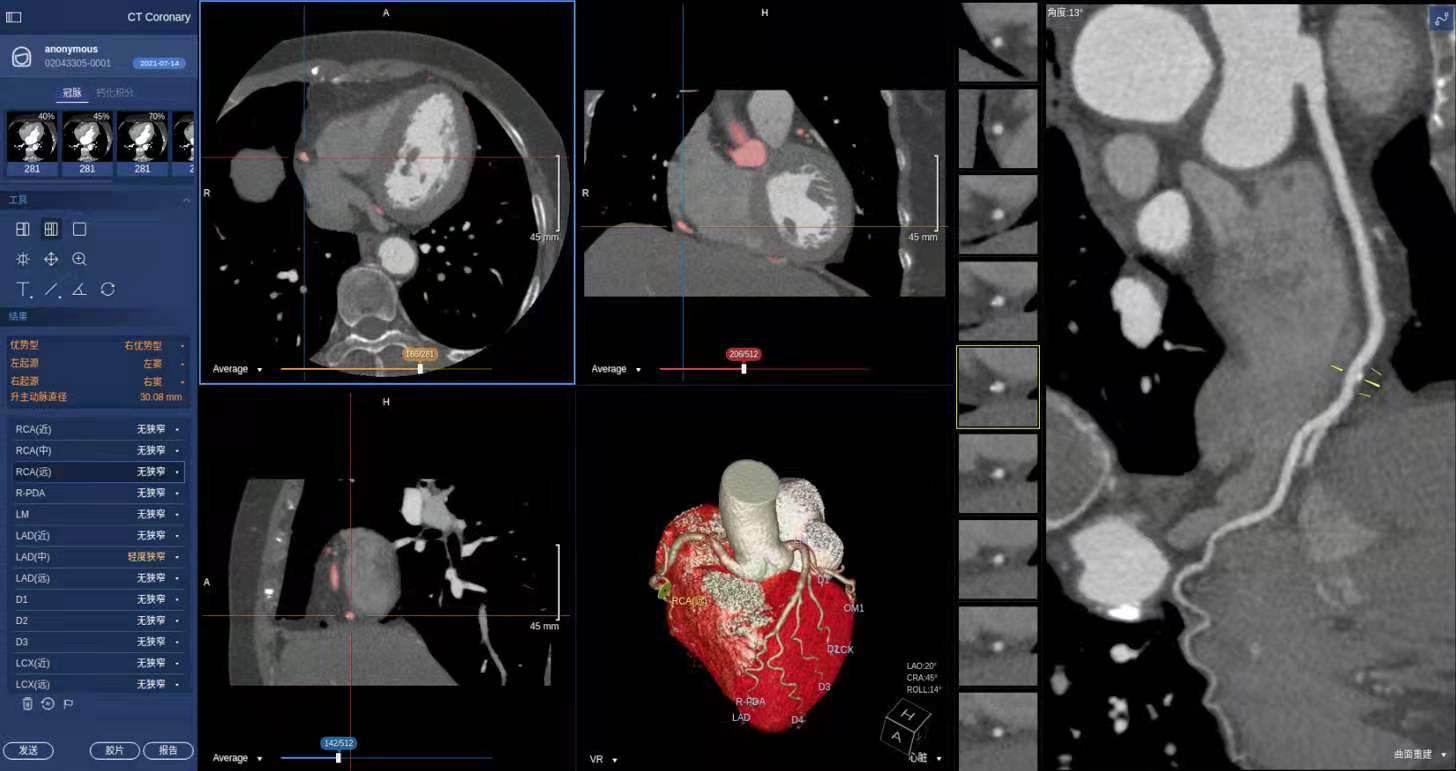

又例如,在心血管疾病诊断领域,基于CTA影像准确地提取血管三维结构是整个诊断流程的首要环节。传统后处理工作站存在细小血管分支提取精度不足的问题,而且需要较多的人工交互,耗时较长。

为此,商汤科技发明了一种新的深度强化学习技术,应用到血管树自动提取,模拟医生或技师手动追踪血管的方式,直接从原始图像中自动提取血管的三维拓扑结构,可以适应不同患者心血管的各种复杂结构,并且达到了媲美专业技师的血管提取准确度和完整性,为冠心病的精准诊断奠定了基础。

此外,心脏的分割与三维重建也是诊断阅片中的重要一环,针对心脏影像空间分辨率高、标注数据难以获取等问题,商汤科技提出了一种小样本学习的分割框架,将半监督学习和自训练方法有效结合,在极少标注数据训练情况下,实现了心脏多腔室的高精度分割,有效帮助医生进行如心肌肥厚、心力衰竭等疾病的预测。相关专利成果均已在SenseCare®Cardiac心脏冠脉智能临床解决方案中得到应用,并发表在医学图像分析顶级期刊及会议。

南京医科大学附属常州第二人民医院是首批应用SenseCare®Cardiac心脏冠脉智能临床解决方案的医院,该院医学影像科、核医学科主任潘昌杰教授介绍说,以往单个冠脉病例的诊断从医生开始阅片到出具报告通常需要耗费15~20分钟,而引入该产品之后,从数据加载到最后胶片打印完成只需3-5分钟,阅片效率得到了显著提升。融入了原创技术的SenseCare®智慧诊疗平台,可以为医生提供高性能的智能辅助,有效提升临床阅片诊断与手术规划的效率。商汤希望以SenseCare®智慧诊疗平台为支点,持续拓展AI在真实临床场景下的创新应用。

SenseCare®Cardiac心脏冠脉智能临床解决方案可自动完成冠脉三维重建并检测斑块与狭窄,将原本需要15~25分钟冠脉CTA阅片流程,缩短至1分钟以内。